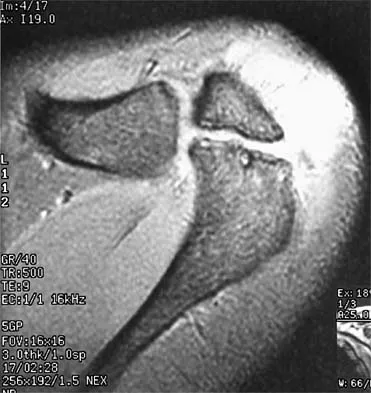

Figure 30 shows an axial T1-weighted MRI scan of a patient's right shoulder. The arrows are pointing to what normal structure?

Explanation

Tears of the pectoralis major tendon are frequently missed during examination. MRI provides excellent visualization of the tendon if the study extends low enough down the arm. The pectoralis major tendon inserts on the crest of the greater tubercle of the humerus, just lateral to the long head of the biceps tendon. The latissimus dorsi tendon inserts medial to the long head of the biceps tendon on the lesser tubercle. The subscapularis tendon inserts on the lesser tuberosity more proximally. The deltoid insertion is more distal. Connell DA, Potter HG, Sherman MF, et al: Injuries of the pectoralis major muscle: Evaluation with MR imaging. Radiology 1999;210:785-791. Carrino JA, Chandnanni VP, Mitchell DB, et al: Pectoralis major muscle and tendon tears: Diagnosis and grading using magnetic resonance imaging. Skeletal Radiol 2000;29:305-313.